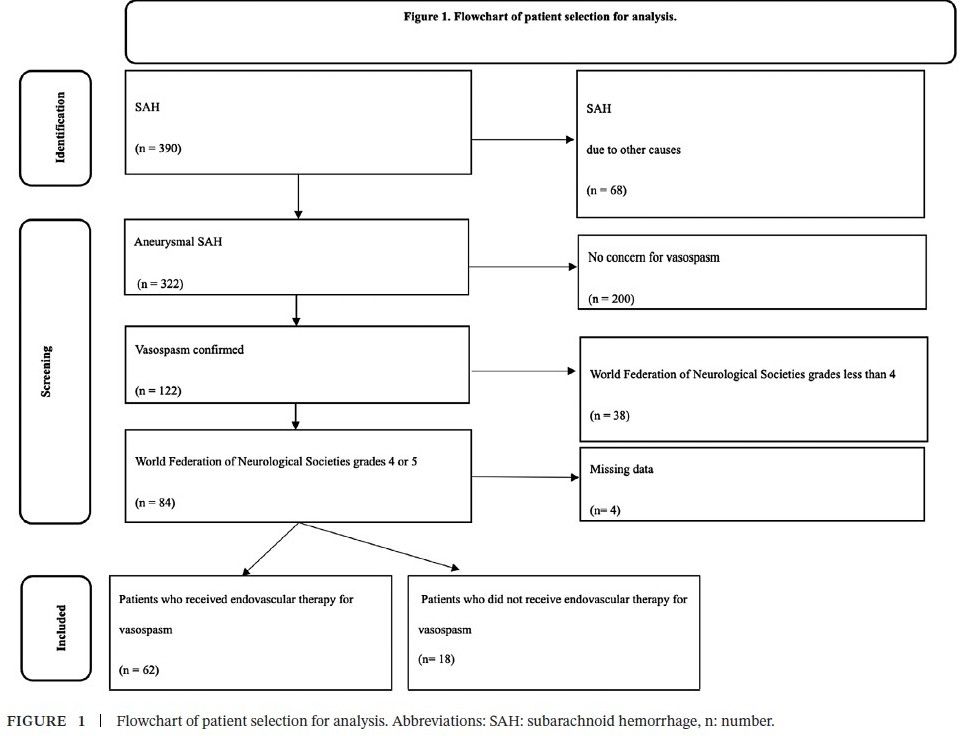

onlinelibrary-wiley-com.ezp-prod1.hul.harvard.edu/doi/epdf/10....

#neuroimaging #neurology #neuroskyence #radiology #subarachnoidhemorrhage #vasospasm #endovasculartherapy

onlinelibrary-wiley-com.ezp-prod1.hul.harvard.edu/doi/epdf/10....

#neuroimaging #neurology #neuroskyence #radiology #subarachnoidhemorrhage #vasospasm #endovasculartherapy